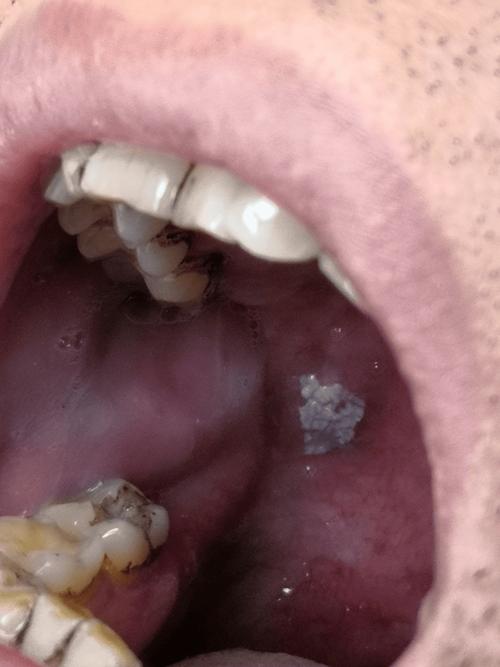

红斑或白斑(“变色”)

这是口腔粘膜的癌前病变,需要高度警惕。

- 特点:

- 红斑: 表现为鲜红色天鹅绒样的斑块,边界清晰,表面光滑或轻微凹陷,触摸时质地较硬,没有明显疼痛感,但易出血。

- 白斑: 是最常见的癌前病变,表现为口腔粘膜上的白色斑块,不能被擦掉,如果白斑表面变得粗糙、增厚、硬结、出现裂纹或溃疡,癌变风险会急剧升高。

- 颗粒状白斑: 尤其是在口底和舌腹部的白色颗粒状区域,癌变风险很高。

- 注意: 并非所有白斑都会癌变,但出现上述变化时,必须立即就医。